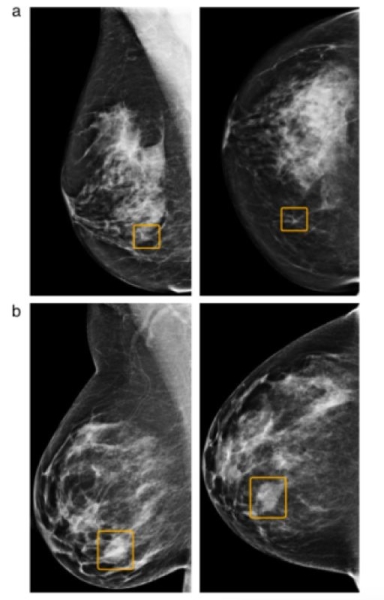

A组:6位人类专家漏检、AI检出的癌症病例;B组:6位人类学家检出、AI漏检的癌症病例。